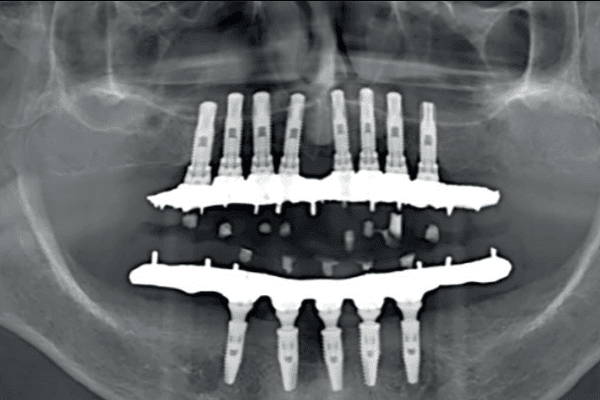

Saiba a diferença entre prótese protocolo superior e inferior e qual delas pode ser a solução para o seu caso...

Prótese protocolo antes e depois: descubra como esse tratamento transforma sorrisos e devolve autoestima. Agende sua avaliação na Odonto Gama.